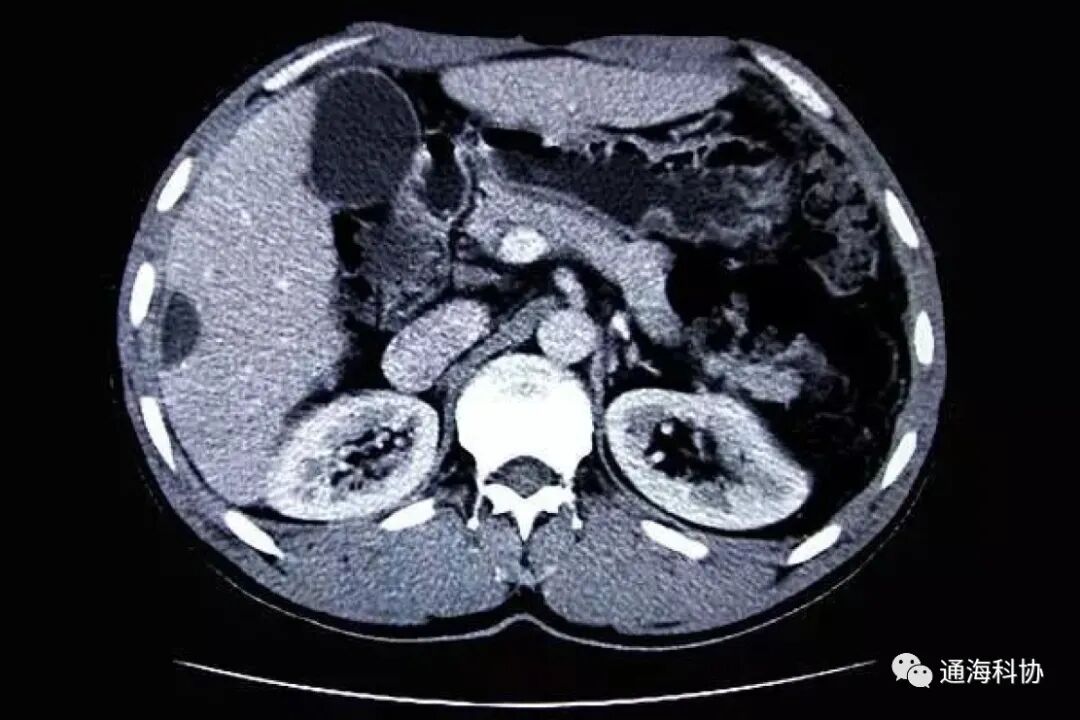

CT是英文Computed Tomography的简称,译意是电子计算机断层扫描。主要采用的检查介质是X射线,通过X射线对身体的穿透性扫描,通过高度灵敏的探测器,得到被扫描部位的影像,具有扫描快,图像清晰的特点。

X射线穿透力极强,在穿透人体时,会根据人体不同组织不同密度形成不同吸收率,在感光胶片上留下灰度不同的黑白影像,医生就可以通过观察分析这些影像,得到人体内部组织的状态,从而做出疾病的诊断。

CT就是在X光透视基础上发展起来的,CT则是通过旋转装置,将人体就像切萝卜片一样进行断层扫描,灵敏度极高的探测器通过旋转装置,接收到穿透的射线,将获得的数据输入到计算机,通过计算机解码后重建图像。

CT设备的主要组成结构有三大部分,即:扫描部分,由X线管、探测器和扫描架组成;计算机系统,将扫描收集到的信息数据进行贮存运算;图像显示和存储系统,将经计算机处理、重建的图像显示在电视屏上或用多幅照相机或激光照相机将图像摄下,用于医生观察。

现在的CT设备已经从最开始的第一代,更新到了第五代,从最开始扫描面积很小,扫描时间长(需要数秒),探测器少(只有一两个),分辨率很低,到如今扫描面积扩大很多,空间分辨率可达0.4mm(毫米),扫描时间缩短到40ms(毫秒),扫描64层图像只需要330ms。

扫描的方式从开始只能平移,到现在能够做平扫、增强扫描和造影扫描,还可以实现三维立体动态图像。